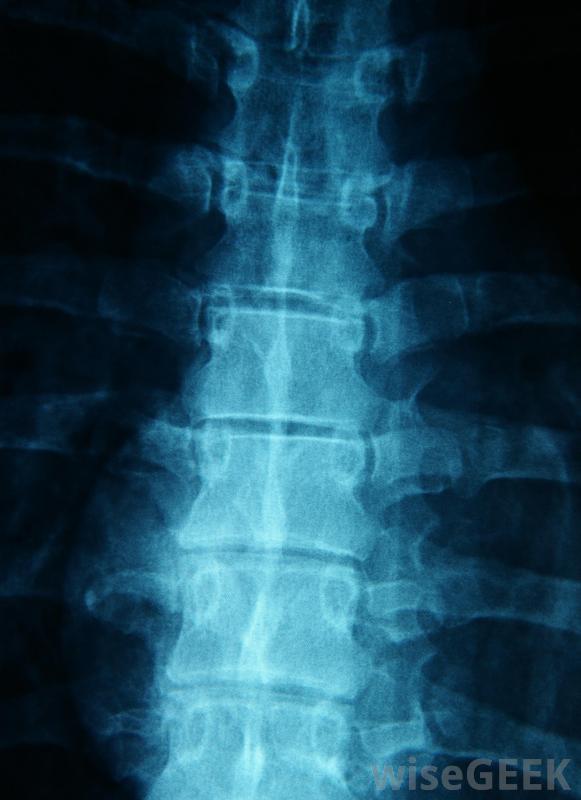

層間硬膜外注射的工作原理是進入包裹脊神經的硬腦膜周圍區域。所有從脊椎進入手臂、腿部和胸部的神經都經過這個區域。注射過程中,針頭直接插入薄膜,將類固醇輸送到狹小的空間。

在層間硬膜外注射過程中,靜脈注射首先輸送麻醉劑,這樣身體就可以放松注射。病人被放在他或她的胃部的x光臺上,注射區域周圍的皮膚被消毒。此時,另一種麻醉劑被注射到注射區進一步放松神經末梢,使其疼痛。一種稱為透視的x光片可以讓醫生將針頭精確地引導到脊椎的正確位置。接下來,進行兩次注射:一種是一種特殊的染料,可以確保類固醇的靶向正確的區域,另一種是類固醇本身,它與另一種麻醉劑聯合使用,以保持患者的舒適。

椎管間硬膜外注射通常用于治療脊柱三個部位之一的炎癥。在頸段硬膜外注射中,類固醇可以減輕頸、肩和臂的疼痛。腰段硬膜外注射會影響下背部、臀部和臀部的疼痛,以及腿部的不適感藥物可以治療上背部、肋骨的炎癥,在某些情況下,腹部。大約50%的患者報告在接受層間硬膜外注射后,患處疼痛明顯減輕。